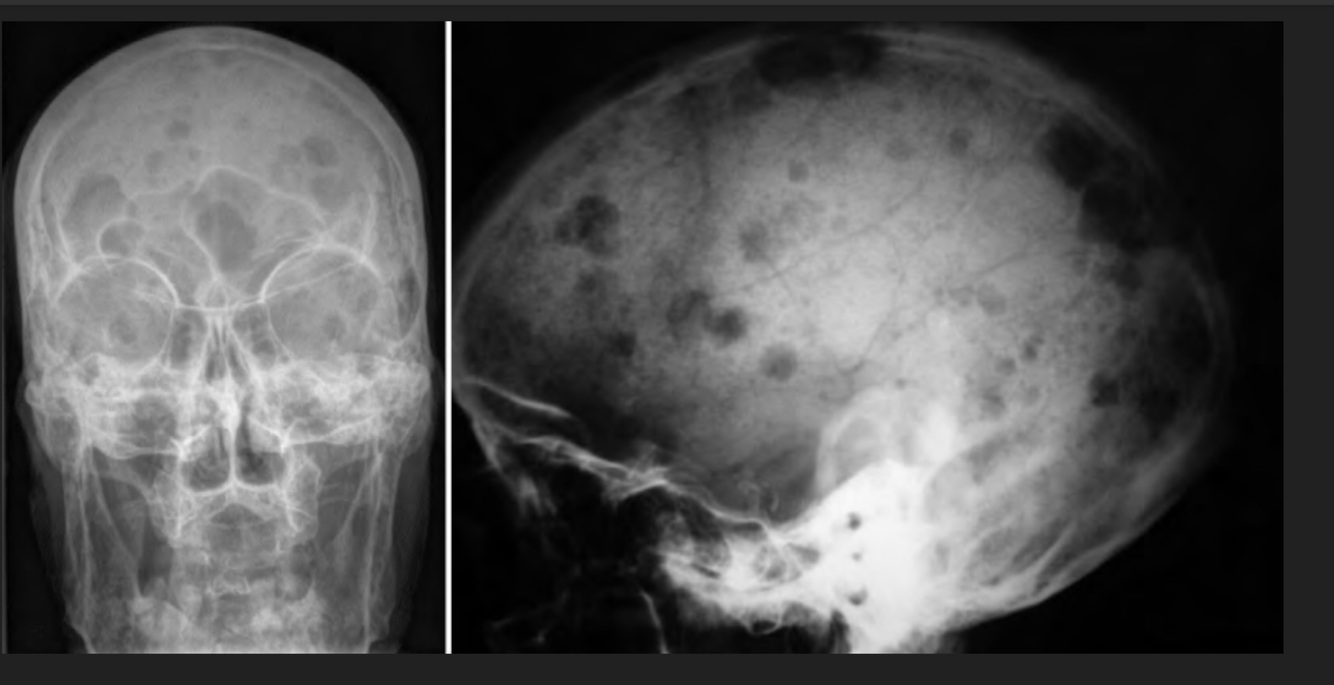

Q

Femenino de 72 años de edad, con cefalea y crisis convulsivas

A

Neurocisticercosis